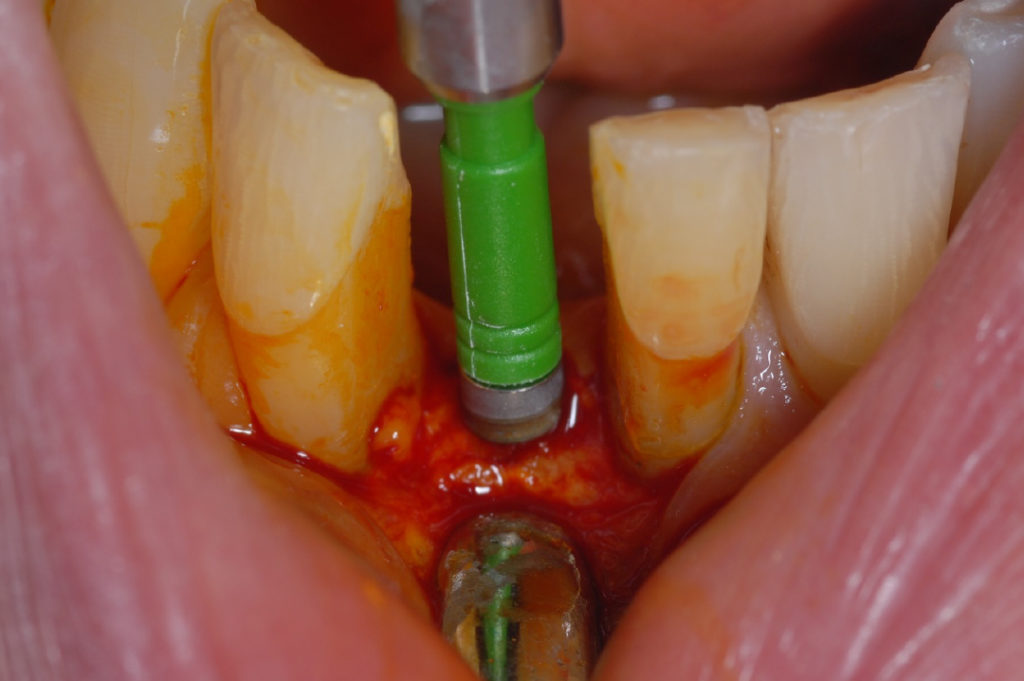

Inserción del implante XCN® 2.9 x 12 mm

Implante en el sitio